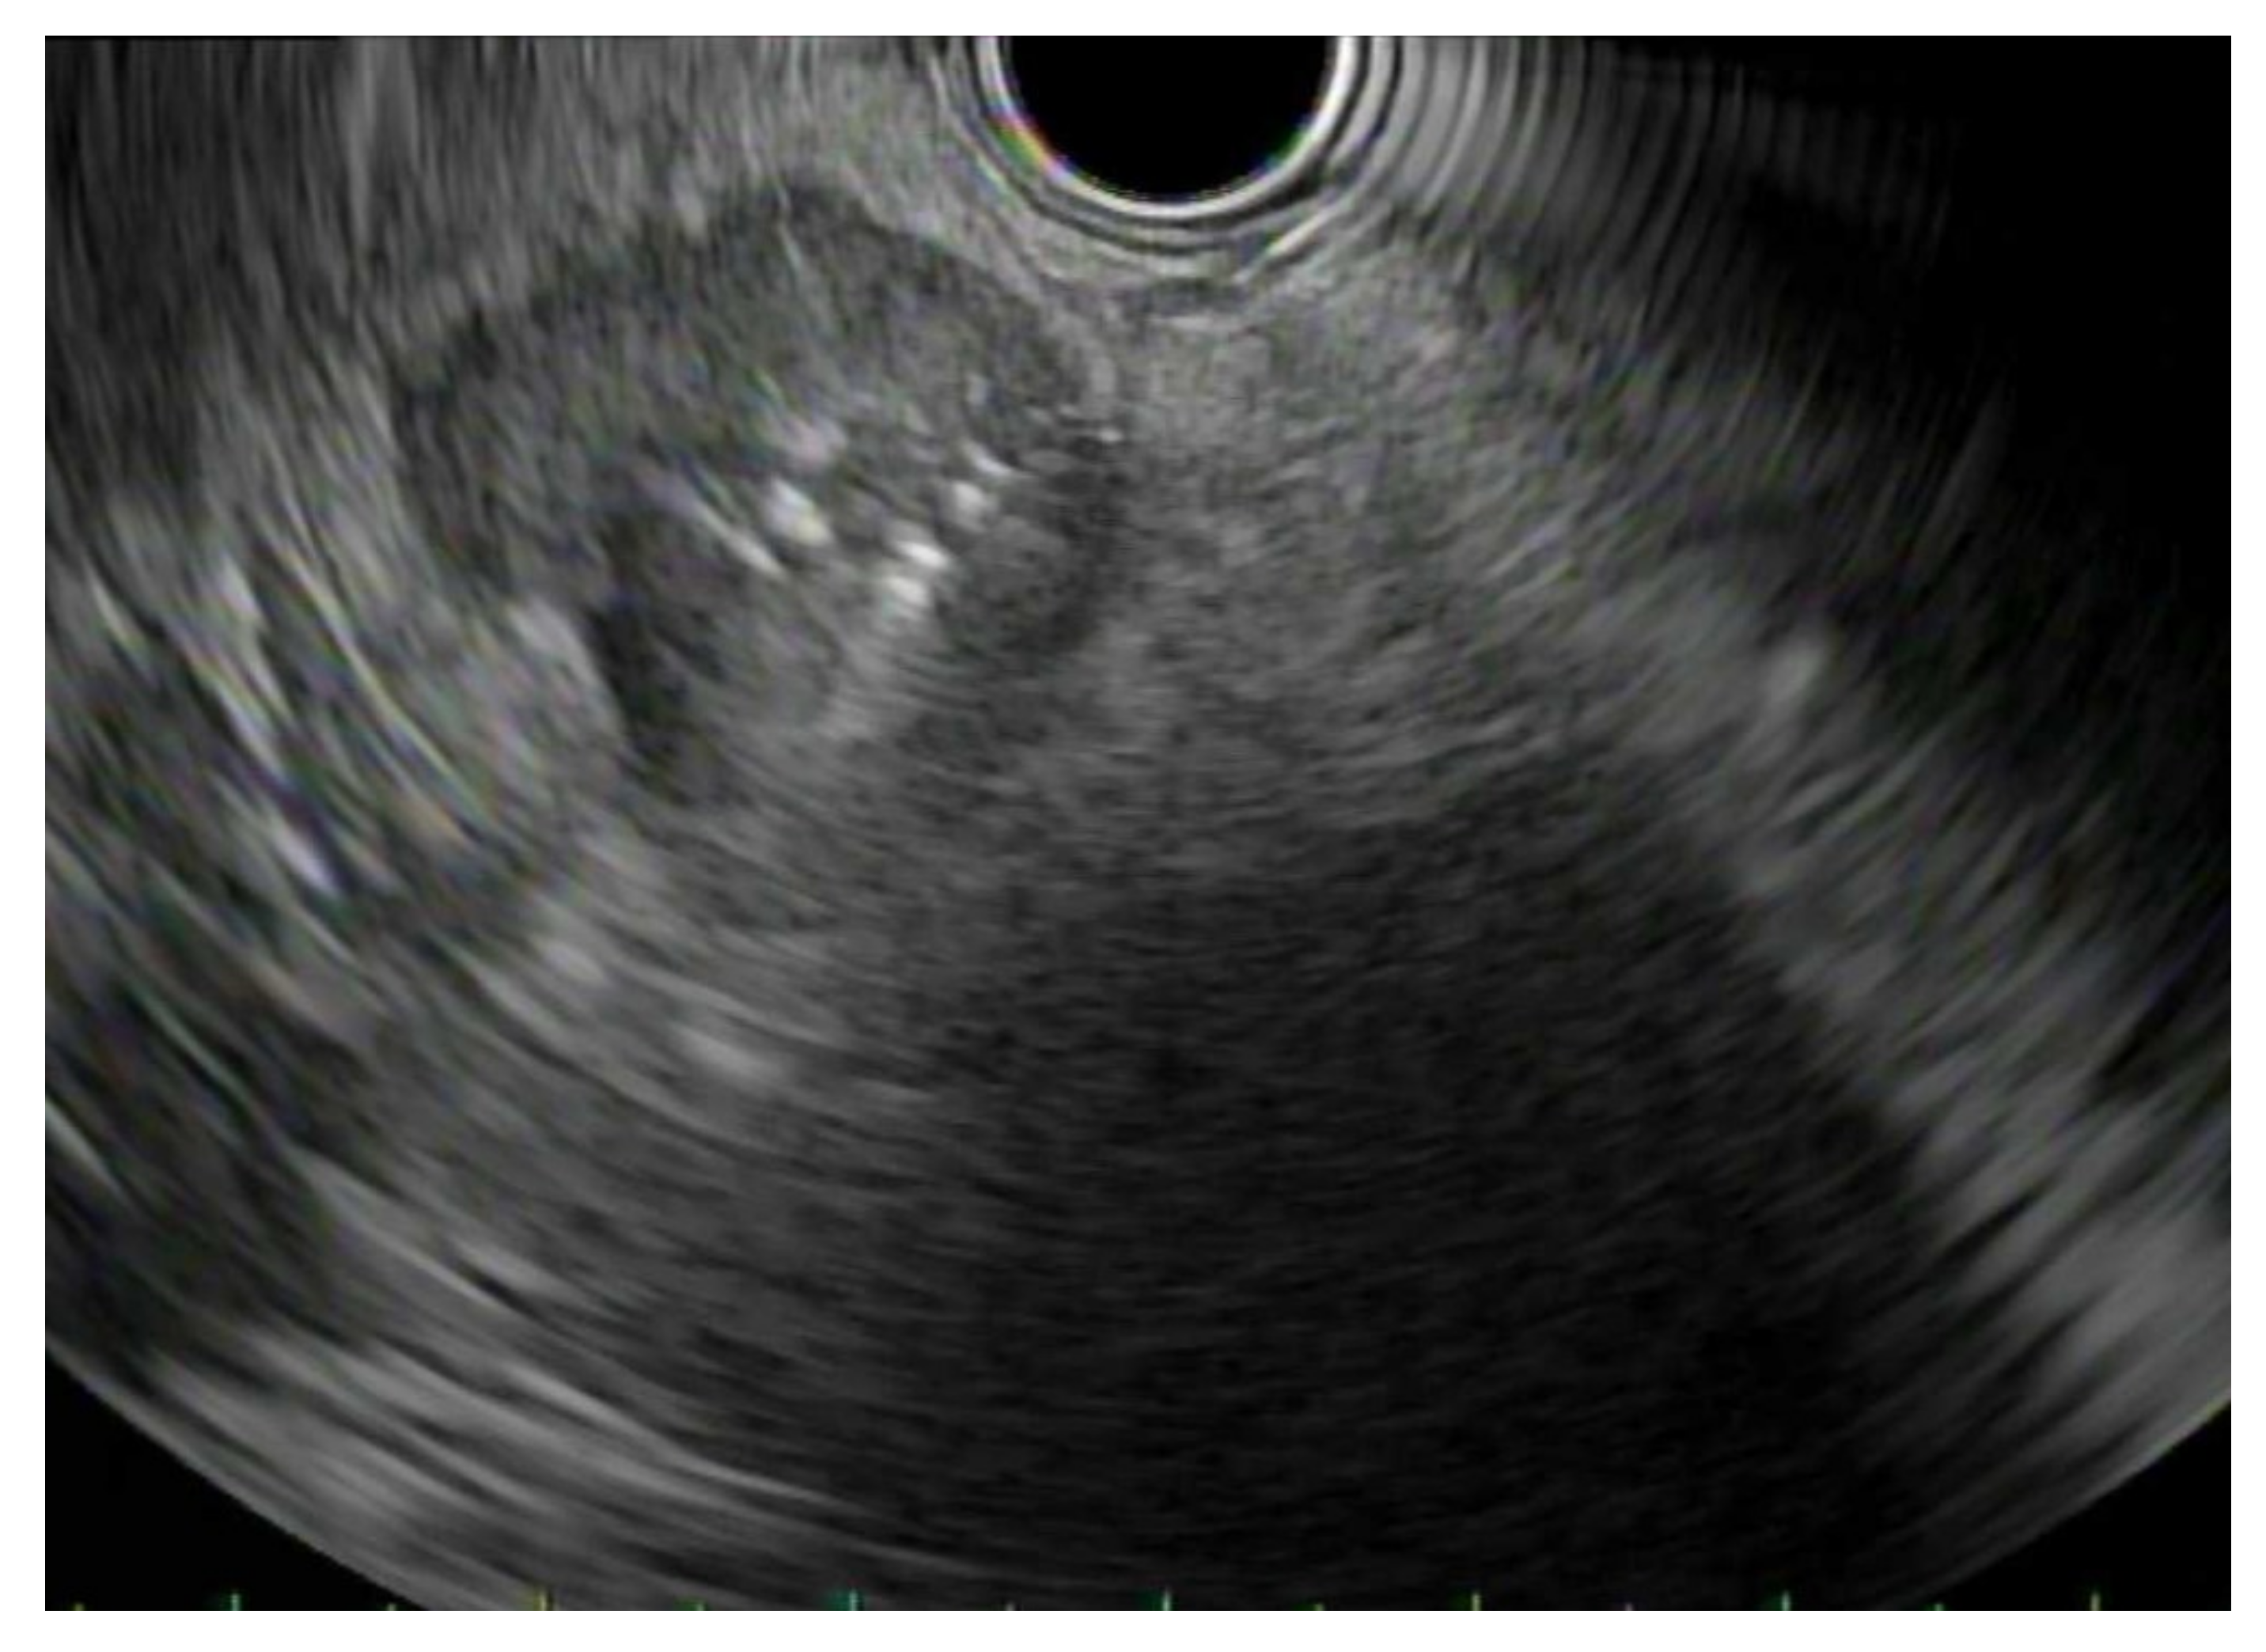

3.1. EUS vs. Percutaneous Biopsy

3.2. EUS-FNA vs. FNB